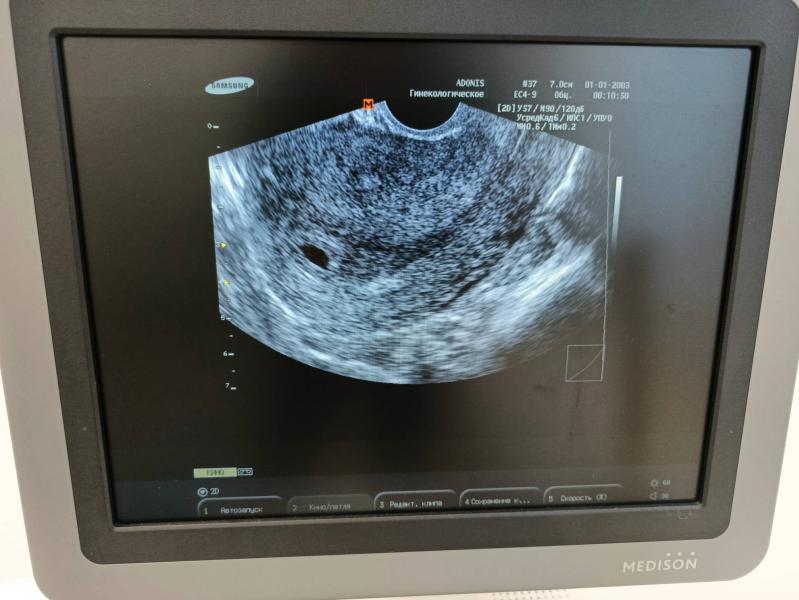

Срок 5 недель и 2 дня

Не выдержала я все таки , сходила сегодня на узи, хотя планировала 2-3 октября

Но т к прошлая беременность была внематочная, очень переживала что будет повторно. Слава Богу , всё там, где должно быть (как сказала врач)

Эмбриона конечно не увидели , сказала рано еще , придти дней через 10 не раньше. Главное есть плодное яйцо и жёлтый мешочек .

Увидела гематому, вроде сказала возможно ничего страшного, но надо понаблюдать. К своему гинекологу записана на 6 октября. Растём дальше 😁